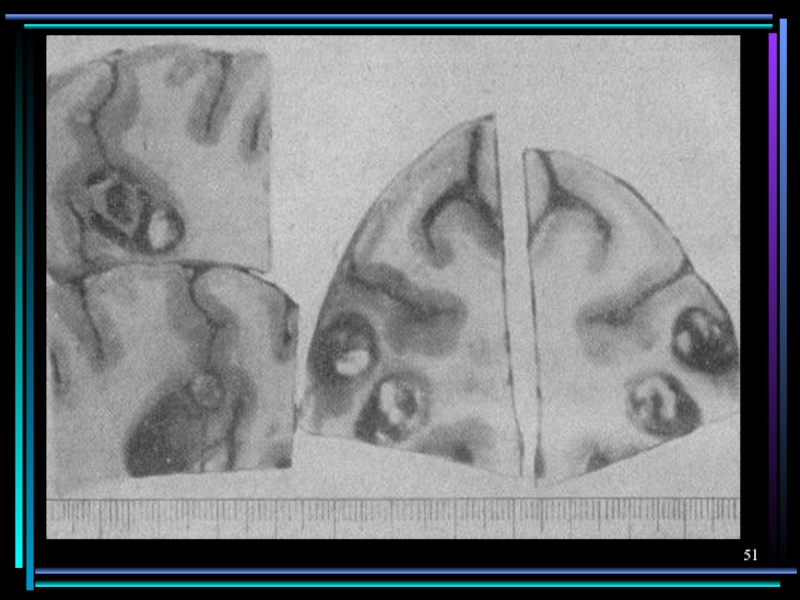

Слайд 47Поражение нервной системы

Трихинеллез

Эхинококкоз

Цистицеркоз

Токсокароз

Стронгило-идоз

Очаговые васкулиты, менингит, под-корковый энцефалит, полинейропатия

Астено-депрессивный синдром, психоз

Симптомы сдавления

вещества голов-ного и спинного мозга, симптомы повышения внутричерепного давления, эпилепсия, энцефалопатия

Гранулемы в головном мозге у детей могут проявляться эпиприступами.

Менингоэнцефалит при выраженном иммунодефиците

Поражение нервной системыТрихинеллезЭхинококкозЦистицеркозТоксокарозСтронгило-идозОчаговые васкулиты, менингит, под-корковый энцефалит, полинейропатияАстено-депрессивный синдром, психозСимптомы сдавления вещества голов-ного и спинного мозга, симптомы